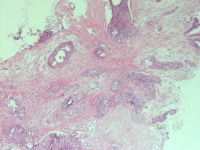

导管内乳头状瘤?恶变?

性别

女

年龄

39岁

发现右乳肿物6月余

右乳肿物

1.5*1*0.5cm灰白不整形组织。

浸润性癌

导管内乳头状癌

需要做肌上皮标记协诊。